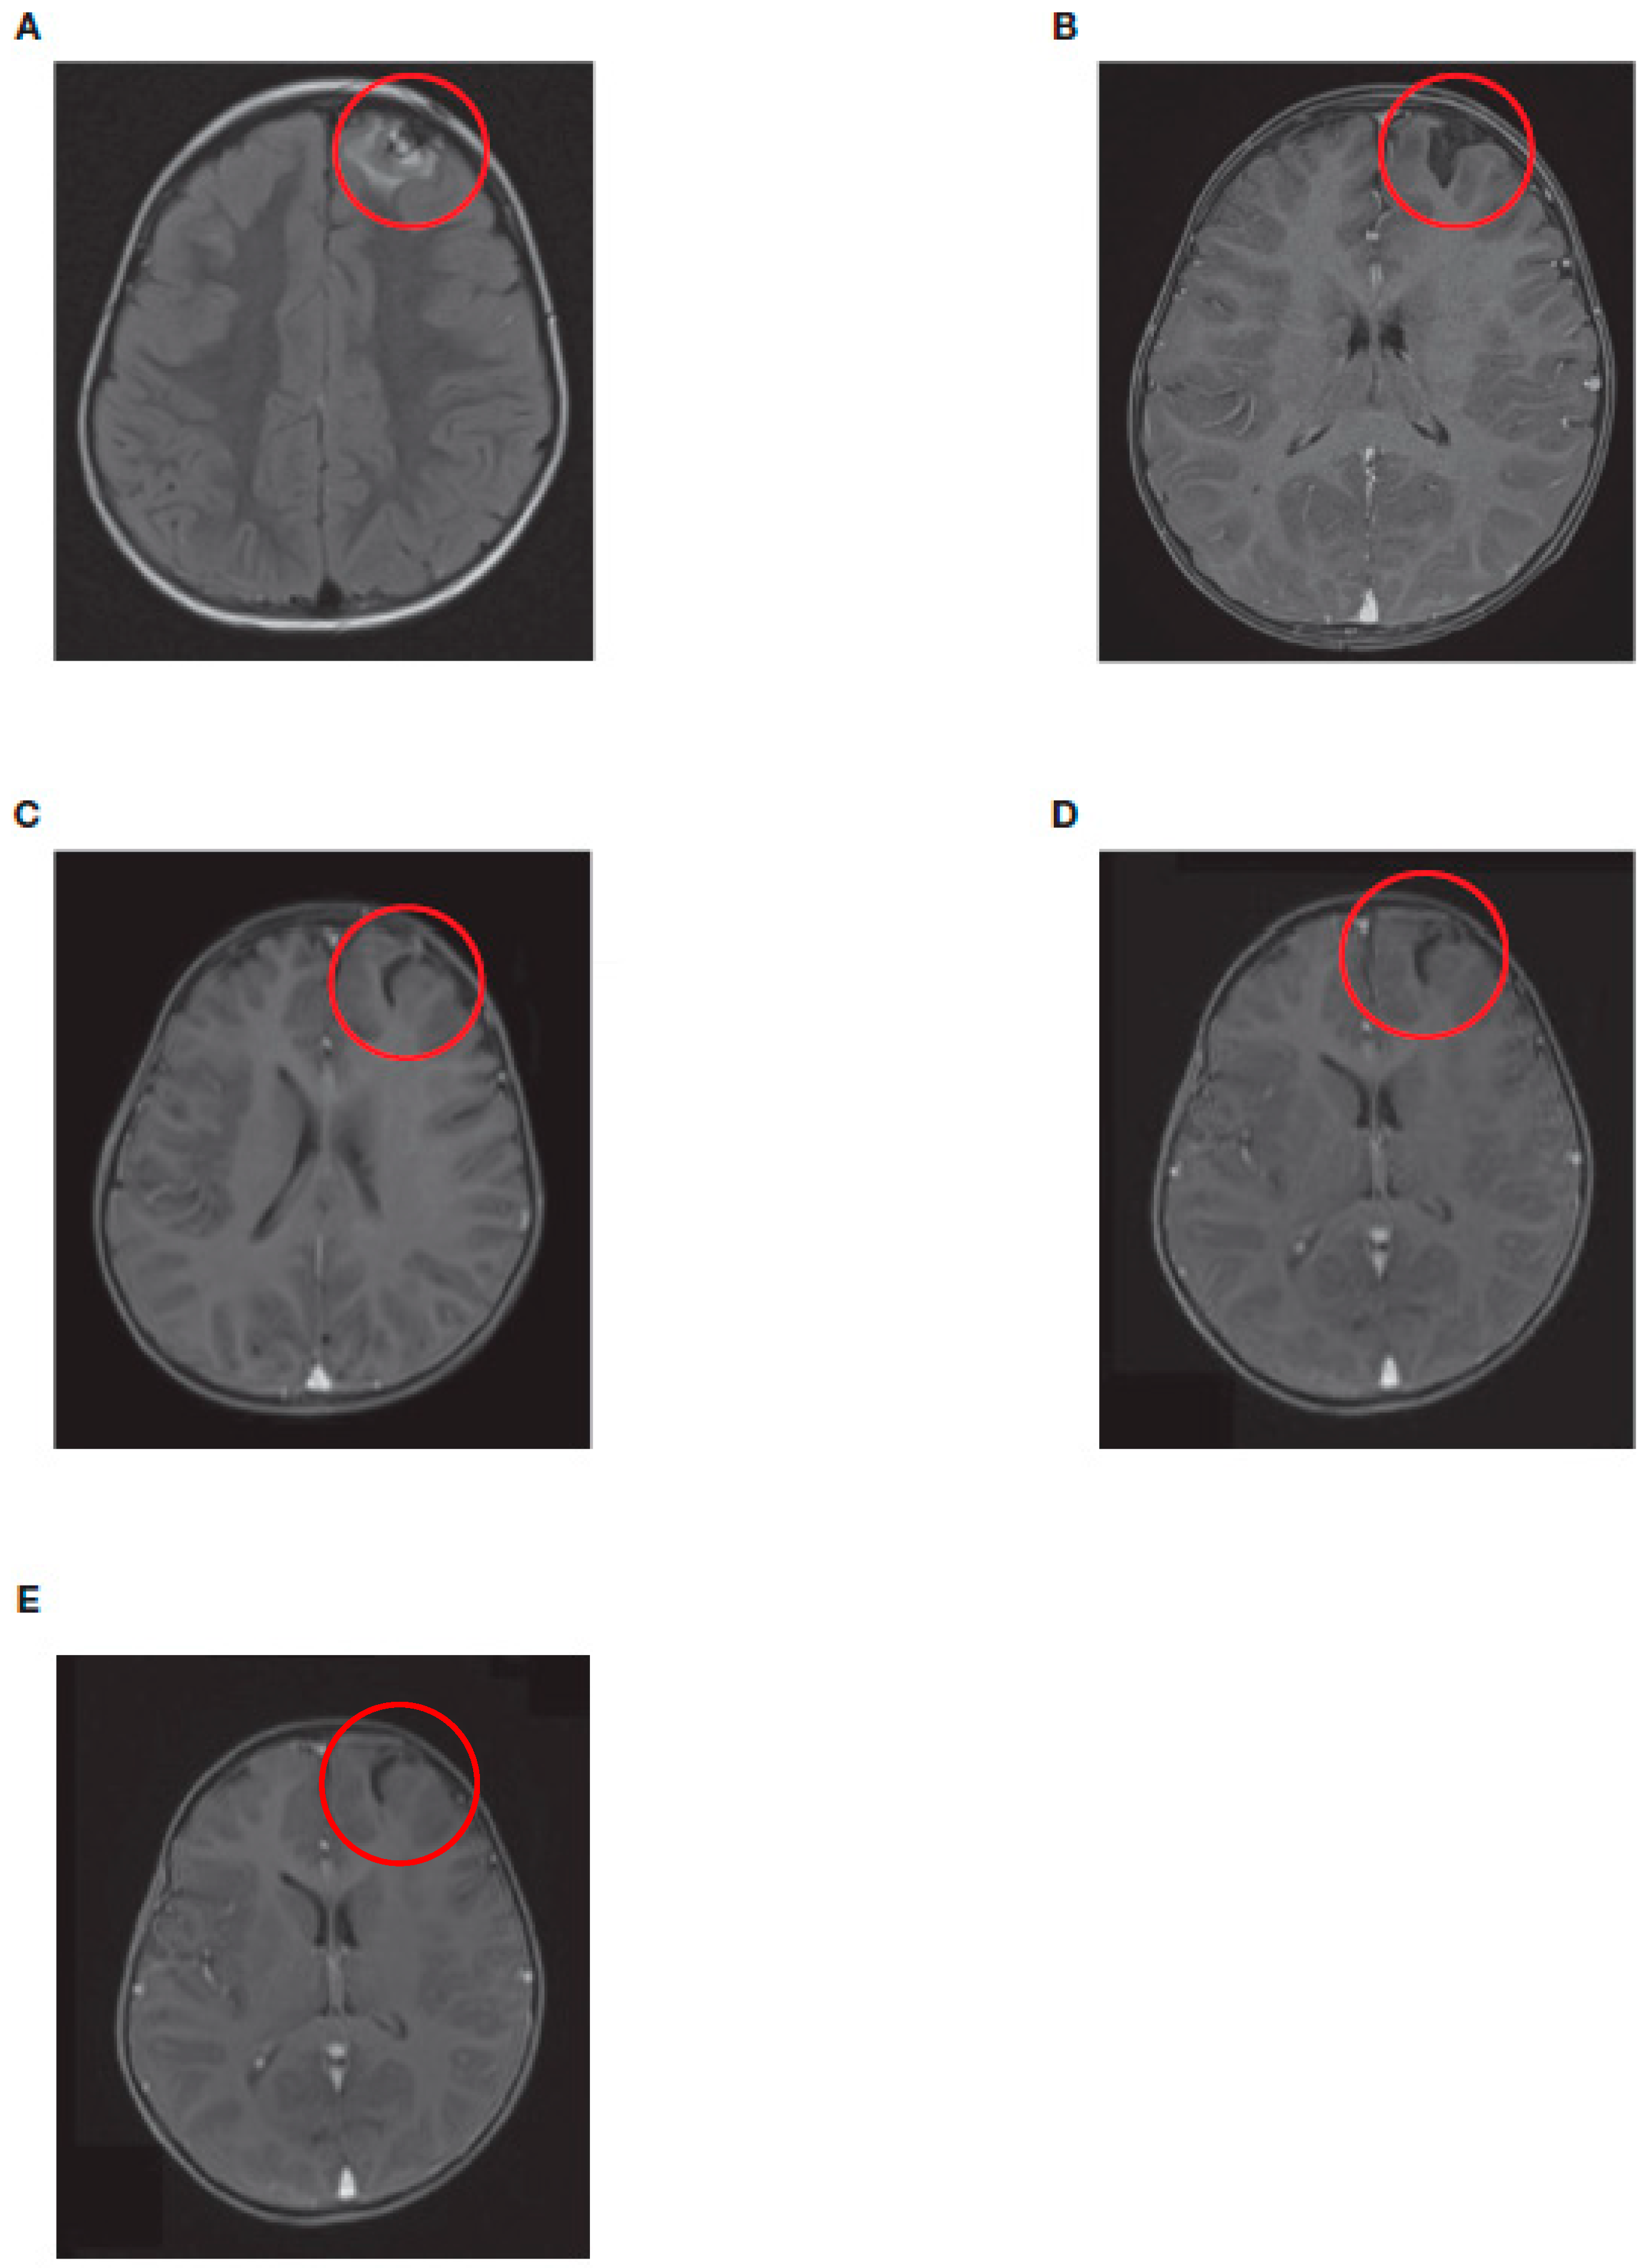

| 1 | 17 | Distant metastases (CNS only) Temporopolar dural metastasis (right cranial fossa) with local hemorrhage |

| 4 | 27 | Distant metastases (CNS only) Intracranial right frontal, left temporal, left frontobasal, involvement of the brain parenchyma, large liquid/hemorrhagic formations, |